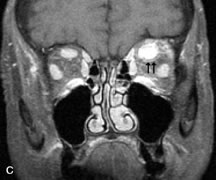

Lymphomas have MRI characteristics similar to those of inflammatory lesions in that they are hypointense to fat and isointense to muscle on T1-weighted images (Fig. 22). They may appear hyperintense to fat on T2-weighted images, perhaps owing to less fibrosis than that seen in orbital inflammatory pseudotumor, although this is not a consistent finding.31,50,66 Lymphoid tumors typically enhance moderately after contrast injection. Unfortunately, studies have shown that tumor density and homogeneity are similar between inflammatory and malignant orbital infiltrates, and MRI cannot differentiate these lesions.72,73

Fig. 22. A and B. T1- and (C) T2-weighted MR scans demonstrate a poorly defined multicompartmental mass enveloping the lateral rectus, superior rectus, and levator palpebrac superioris muscles. The lesion is isointense to brain on T1- and T2-weighted scans, as is typical for highly cellular neoplasms. D. Postcontrast fat-suppressed T1-weighted scan demonstrates intense enhancement of the infiltrating intraconal and extraconal tumor.